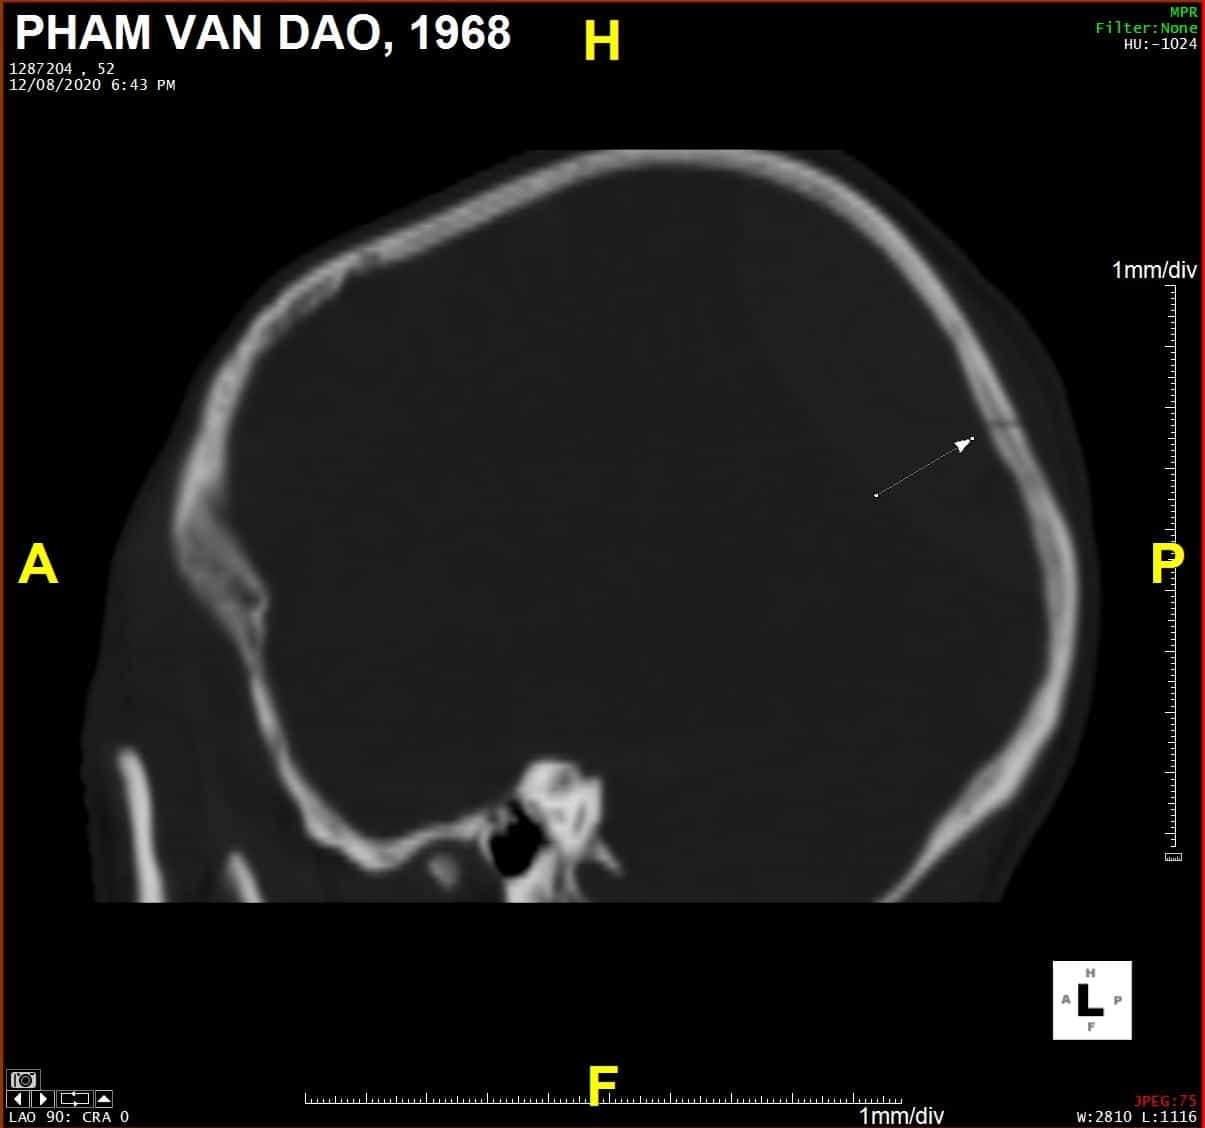

Chấn thương sọ - Ảnh 3

Sagittal

» Thông tin: Nam giới – 52 tuổi.

» Lâm sàng: Chấn thương sọ não.

# Tụ máu ngoài màng cứng vùng chẩm phải / Vỡ xương chẩm phải: đường vỡ thẳng (Linear fracture) không thấy rõ trên hướng cắt Axial => quan sát rõ trên hướng cắt Coronal và Sagittal.